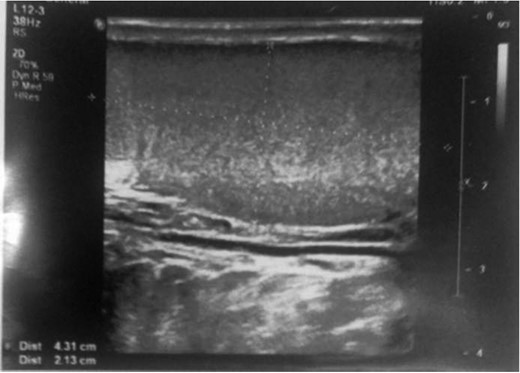

Ultrasound picture of the testis showed normal echogenicity without any abnormality.

Doppler ultrasound using gray scale method of the testis showed normal flow pattern of testicular artery.